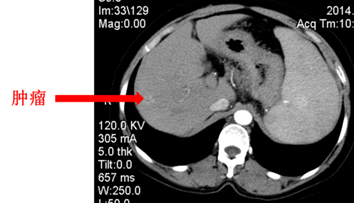

患者赵XX,女,54岁,因“发现白细胞及血小板低1年”2014年入院。

入院检查

CT:符合肝硬化并脾大改变,肝右叶占位,胃底静脉及脾静脉曲张。

临床诊断:右肝占位性病变肝硬化、门静脉高压、脾大脾功能亢进食管胃底静脉曲张